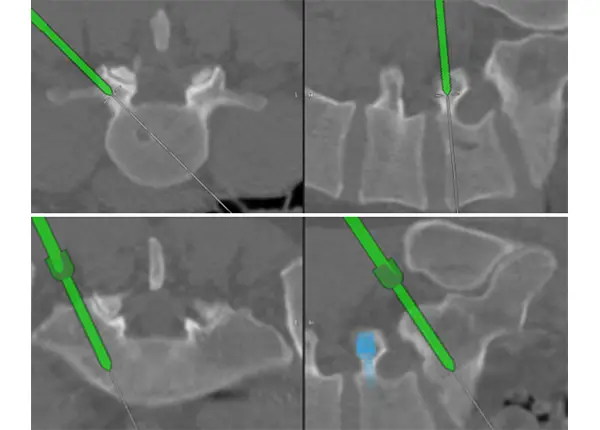

Placement of screws for the fusion using stereotactic 3D navigation.

Using 3D stereotactic navigation, which allows surgeons to see structures deep in the spine that you otherwise cannot see, we employed a microsurgical technique to remove the tumor first and then address the subsequent nerve compression it had caused. We also had to stabilize the spine and accomplished that by inserting minimally invasive instrumentation through that same incision. For the spinal stenosis, we removed the portion of the lamina that was compressing the nerves at L4-L5 and then inspected the spinal cord and nerve roots for any further damage before finally completing the surgery. We essentially performed three operations in one.